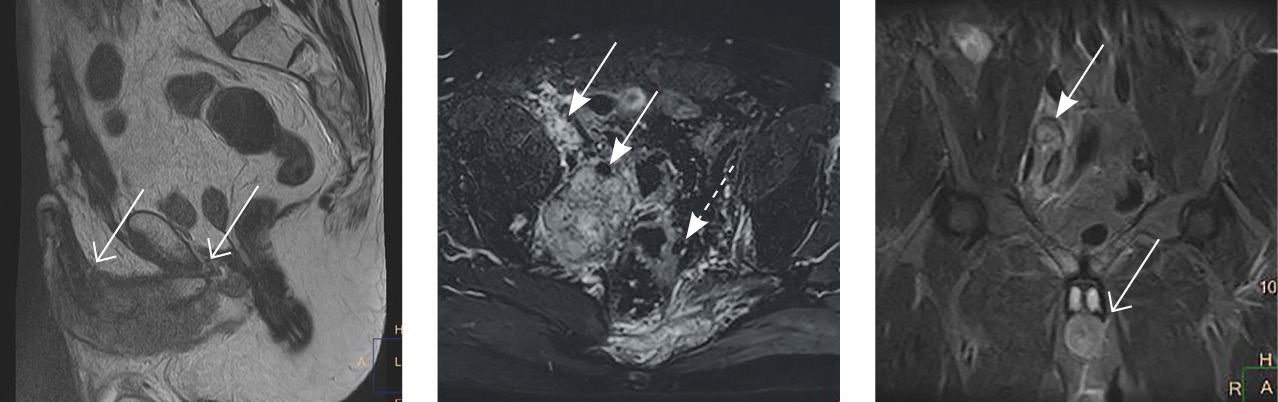

Пациент З. мужского пола 38 лет. Появление гематурии отметил в январе 2019 г. При магнитно-резонансной томографии (МРТ) малого таза обнаружена опухоль в области дна и тела мочевого пузыря размером 65 × 25 мм с наличием инвазивного компонента (рис. 1). Пациенту выполнена цистоскопия с ТУР-биопсией – диагностирована инвазивная уротелиальная карцинома с распространением на шейку мочевого пузыря. В урологическом отделении ГБУЗ МО МОНИКИ им. М.Ф. Владимирского 24.07.2019 выполнена цистпростатвезикулэктомия с двусторонней регионарной (подвздошные и обтураторные лимфоузлы) лимфодиссекцией и последующей гетеротопической реконструкцией мочевого резервуара по Брикеру.

Рис. 1. На серии томограмм малого таза в режимах Т2 и Т2 в режиме Stir в сагиттальной, коронарной и аксиальной проекциях определяется диффузное опухолевое поражение мочевого пузыря, стенка с признаками инвазии мышечного слоя. Регионарные лимфатические узлы без признаков поражения